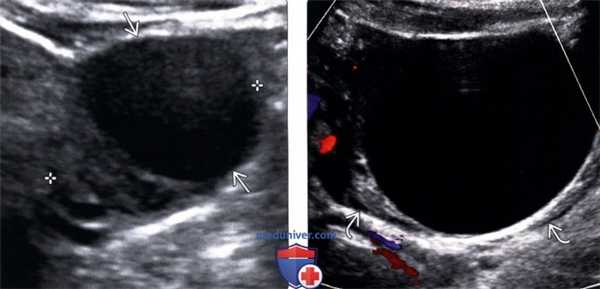

(Слева) УЗИ органов малого таза: типичная картина анэхогеной функциональной кисты с окружающей паренхимой яичника (отмечена калиперами).

(Справа) Функциональные кисты яичника могут увеличиваться, тогда окружающая паренхима яичника сжимается до тонкого ободка. Когда имеются такие проявления, как тазовая боль, необходимо использовать импульсную допплерографию для оценки форм колебаний артериального и венозного кровотоков.